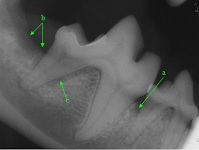

b

Abbreviation

Anatomy

a

enamel

e

cemento-enamel junction

dentin

f

rootcanal system

c

periodontal ligament space

g

mandibular canal

d

lamina dura

h

ventral cortex